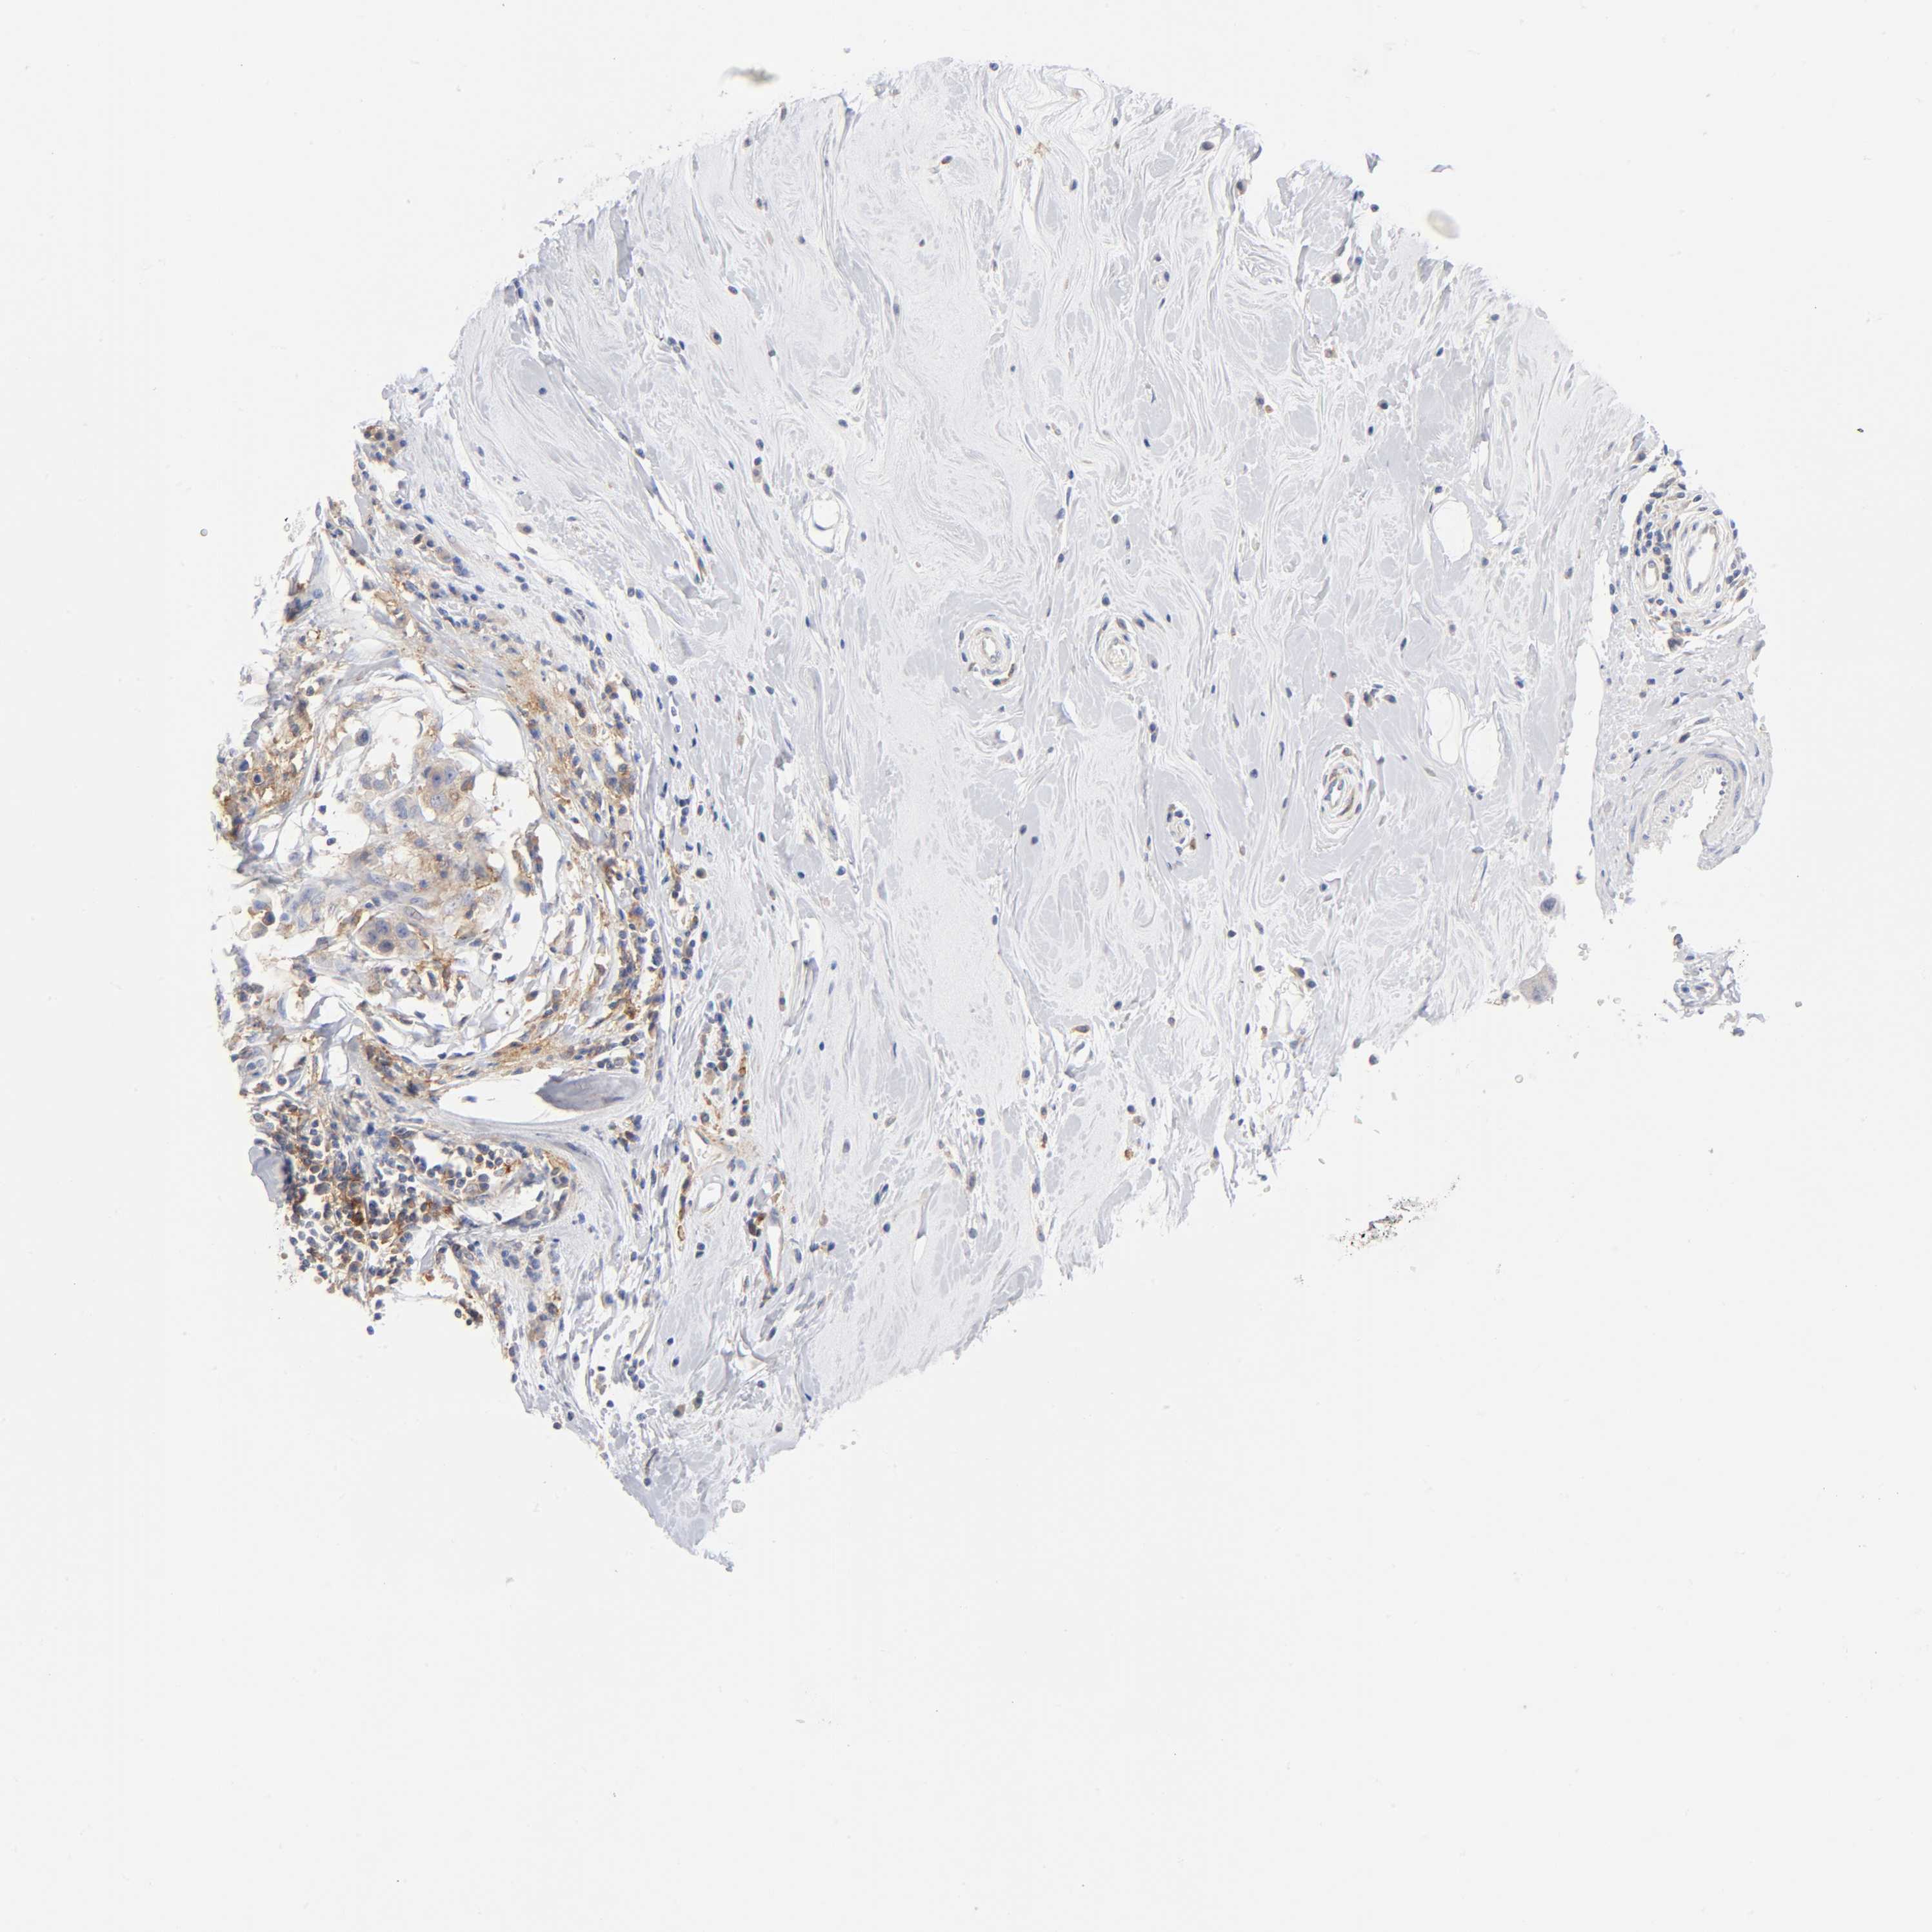

CANCER BREAST CANCER Show tissue menu

BRCA TCGA BRCA VALIDATION PROTEIN EXPRESSION

Breast cancer

Human cancer